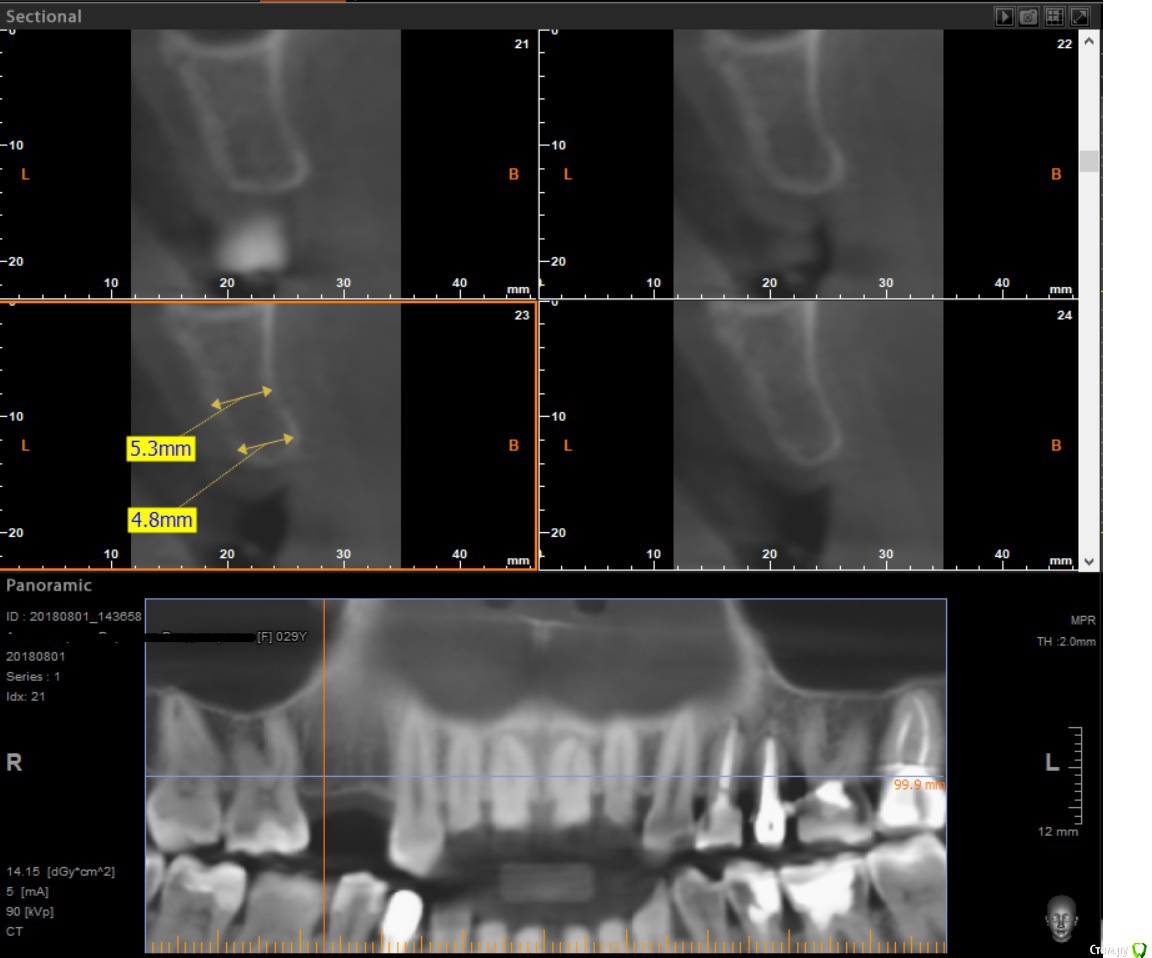

x4ex Опубликовано 29 августа, 2018 Поделиться Опубликовано 29 августа, 2018 (изменено) По всей видимости между экваторами 13 и 16 там около 10мм. Исходя из этого, я бы пошёл по 3 варианту с одним имплантатом нормальной ширины в области 15, только без немедленной нагрузки. Изменено 29 августа, 2018 пользователем x4ex Ссылка на комментарий

kamranchick Опубликовано 29 августа, 2018 Поделиться Опубликовано 29 августа, 2018 Можно ещё посмотреть как получится если через шаблон поставить астру 3.02 штуки Либо Штрауманн 2.9 2 штуки.Без Нкр с сст Ссылка на комментарий

Тимур86 Опубликовано 29 августа, 2018 Поделиться Опубликовано 29 августа, 2018 ощущение что Вы чуть недомерили кость Ссылка на комментарий

Foxtrot Опубликовано 29 августа, 2018 Автор Поделиться Опубликовано 29 августа, 2018 ощущение что Вы чуть недомерили кость прошу прощения. Без очков не вижу Ссылка на комментарий